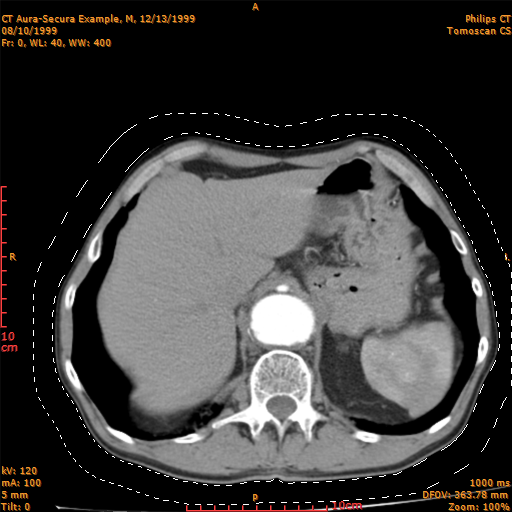

There are seven selection tools available in the program: the Rectangle tool, the Polygon tool, the Circle tool, the Ellipse tool, the Free Hand tool, the Magic Wand tool, and the Eyedropper tool. With these tools you can select a portion of an image. With any of these tools you can create a new selection, add to an existing selection, subtract from a selection, or select an area intersected by other selections. The selected area is marked with a dashed, rotated, black and white line. You can use the selection tools to measure area and volume of the selected portion or to make a statistical analysis (maximum, minimum and mean values standard deviation etc.). You can export the selected area to a text file (in form of X position, Y position, Value) for further analysis with other programs (e.g. MATLAB or ANSYS).